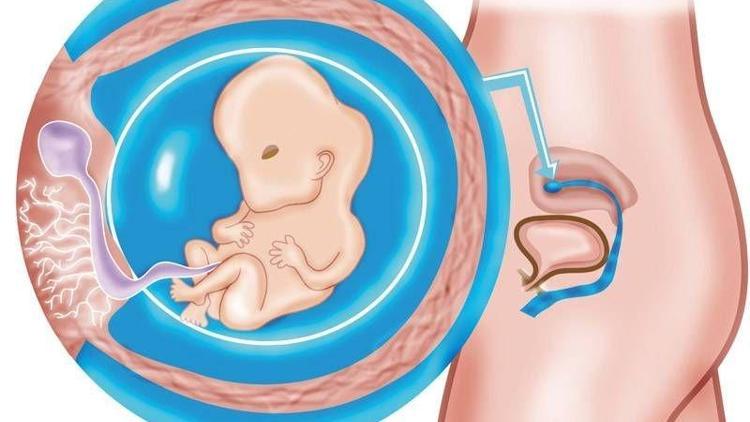

Hamilelikte 8. hafta

Hamileliğinizin 8. haftasında vücudunuz ve bebeğinizdeki gelişmeler neler?

Bebeğiniz artık hareket ediyor ve yer değiştiriyor

Bebeğinizin el ve ayaklarından perde şeklinde parmakları çıkmaya başladı bu hafta. Yavaş yavaş nefes borusu genişlemeye, kuyruğu da yok olmaya başlar. Beyninde, sinir yollarını şekillendiren sinir hücreleri oluşmaya ve kollara ayrılmaya başlar. Şu an bebeğinizin cinsiyetiyle ilgili hayaller kuruyor olabilirsiniz ancak biraz daha sabretmek zorundasınız. Çünkü bebeğinizin dış genital organları henüz oluşmadı. Bir fasulye tanesi kadar olan bebeğiniz, siz her ne kadar hissedemeseniz de artık hareket ediyor ve yer değiştiriyor.